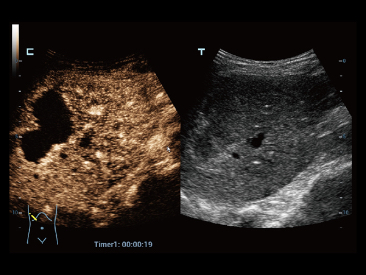

Desde que a empresa foi fundada, a Mindray est├Ī continuamente explorando novas maneiras de melhorar a confian?a no diagn├│stico. Alimentada pela mais revolucion├Īria tecnologia ZONE Sonography?, a nova plataforma Resona 7's ZST+ traz uma qualidade de imagem ultra-som a um n├Łvel superior por aquisi??o de zona e processamento de dados do canal.

Assim como o n├Łvel de qualidade de imagem premium, o Resona 7 tamb├®m melhora as capacidades de investiga??o cl├Łnica com o revolucion├Īrio Fluxo V para avalia??o hemodin?mica vascular e a aquisi??o de plano mais inteligente do conjunto de dados 3D para diagn├│stico CNS fetal. Combinando a opera??o mais intuitiva baseada em gesto de multi-toques e todos os recursos cl├Łnicos essenciais, Resona 7 est├Ī realmente conduzindo novas ondas na inova??o de ultra-som.